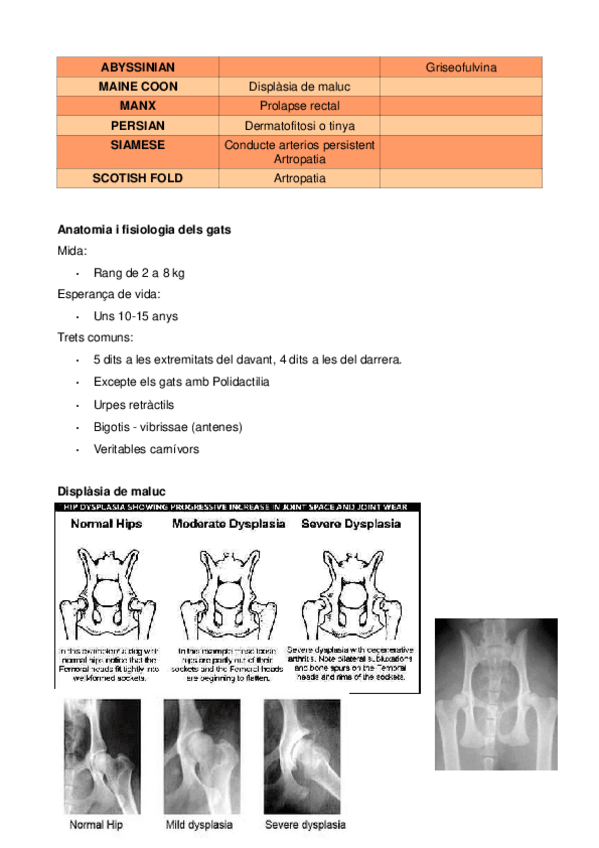

He publicado nuevos apuntes de 1º Apuntes Variados: Gatos.pdf

5 páginas